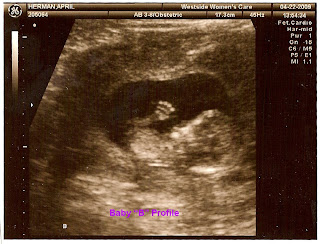

12 1/2 week Ultrasound

Yesterday I had my 12 week Sequential screening. they have to do a bunch of measurements on the babies to see if they may have down syndrome or spina bifida. Anyway, the technician doing the ultrasound was really nice. She spent like 45 minutes with us. Well, of course being my children, the babies wouldn't cooperate with her, so she couldn't get correct measurements. I had to get up, walk around go to the bathroom. Then the 2nd go around, she got great measurements and they look fine:) As you can see, Baby B was the Ham of the day, it just kept posing for shot after shot(She thinks this baby may be a boy:))But Baby A was being shy and was curled up and facing down, so we couldn't get any profile shots. Bummer. The tech couldn't tell what Baby A might be, but I am sticking with Bailey's prediction of 1 boy and 1 girl:) Anyway, all is well with me, I am so happy. Until next time:)